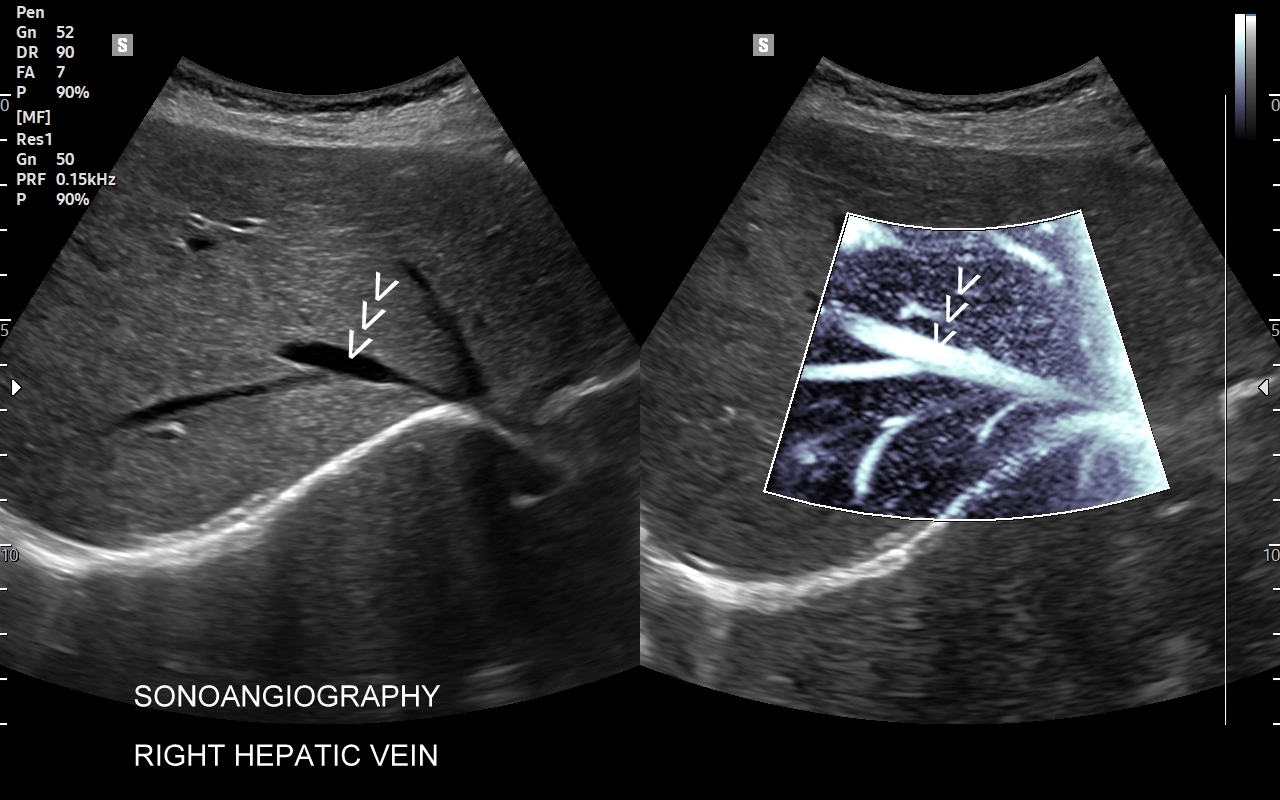

Wątroba posiada unaczynienie różnego typu, a każde o swojej indywidualnej charakterystyce. Są to unaczynienie tętnicze, unaczynienie wrotne (żyła wrotna i jej dopływy z narządów jamy brzusznej), odpływ żylny poprzez żyły wątrobowe. W USG Doppler przepływów wątrobowych bada się każdy z tych układów.

Badanie USG Doppler układu wrotnego wątroby łącznie ze standardową oceną morfologii wątroby i śledziony wykonywane jest najczęściej w ramach diagnostyki nadciśnienia wrotnego, czyli podwyższonego ciśnienia krwi w żyle wrotnej, które może być przyczyną zagrażających życiu żylaków przełyku. Badanie dopplerowskie wątroby uzupełnia również diagnostykę marskości wątroby oraz służy wykrywaniu takich patologii jak zakrzepica w żyle wrotnej i jej dopływach, zakrzepica w żyłach wątrobowych, czy rozprzestrzeniające się nowotwory w naczyniach wątroby.